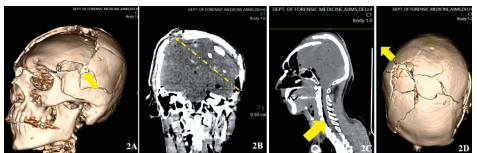

Description: 2A: Communited fracture surrounding the entry. 2B: PMCT (coronal) head - Pneumocranium and displacedbone fragments. 2C: Pneumorrhachis. 2D: Communited fracture of skull vault along the direction of bullet.